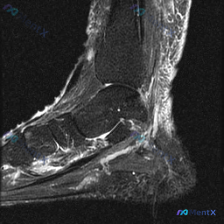

分享一例足部MRI T2加权矢状位读片,整理了完整思路和大家讨论。 病例基本影像信息 本次分析的是足部MRI T2加权矢状位图像,原始问题是观察是否存在软骨异常,我们先把所有影像发现整理清楚: 1. 骨骼结构:跟骨、距骨、舟骨、楔骨及跖骨结构完整,骨皮质连续,未见骨折线;骨髓信号整体正常,未见弥漫性...

给大家分享一份足部矢状位T2加权MRI的读片分析,原始问题是询问图像中观察到的软骨异常,整理一下完整的分析思路: 一、先整理影像的基本发现 这份MRI可见胫骨远端、距骨、跟骨、舟骨、楔骨及部分跖骨,踝关节、距下关节及跗骨间关节对位基本正常,关节面轮廓完整,没有明确骨质破坏或骨折线,跟腱走行和信号都正...